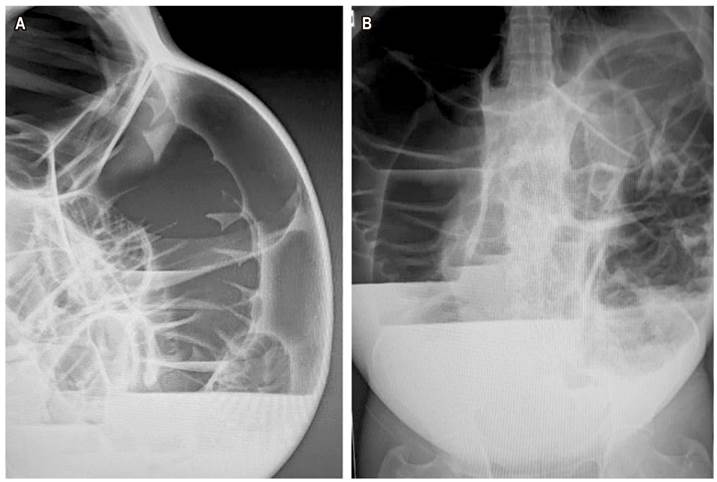

Al ingreso, paciente afebril, hidratado, taquicárdico, con abdomen francamente distendido, timpánico, con ruidos peristálticos presentes con disminución de tono y frecuencia, no presenta dolor. Tacto del recto con ampolla rectal vacía y esfínter anal hipotónico. Se realizan radiografías de abdomen (Figura 1). Se considera franca distensión de asas, que condicionan un colon crítico, por lo cual se indica intervención quirúrgica de urgencia.